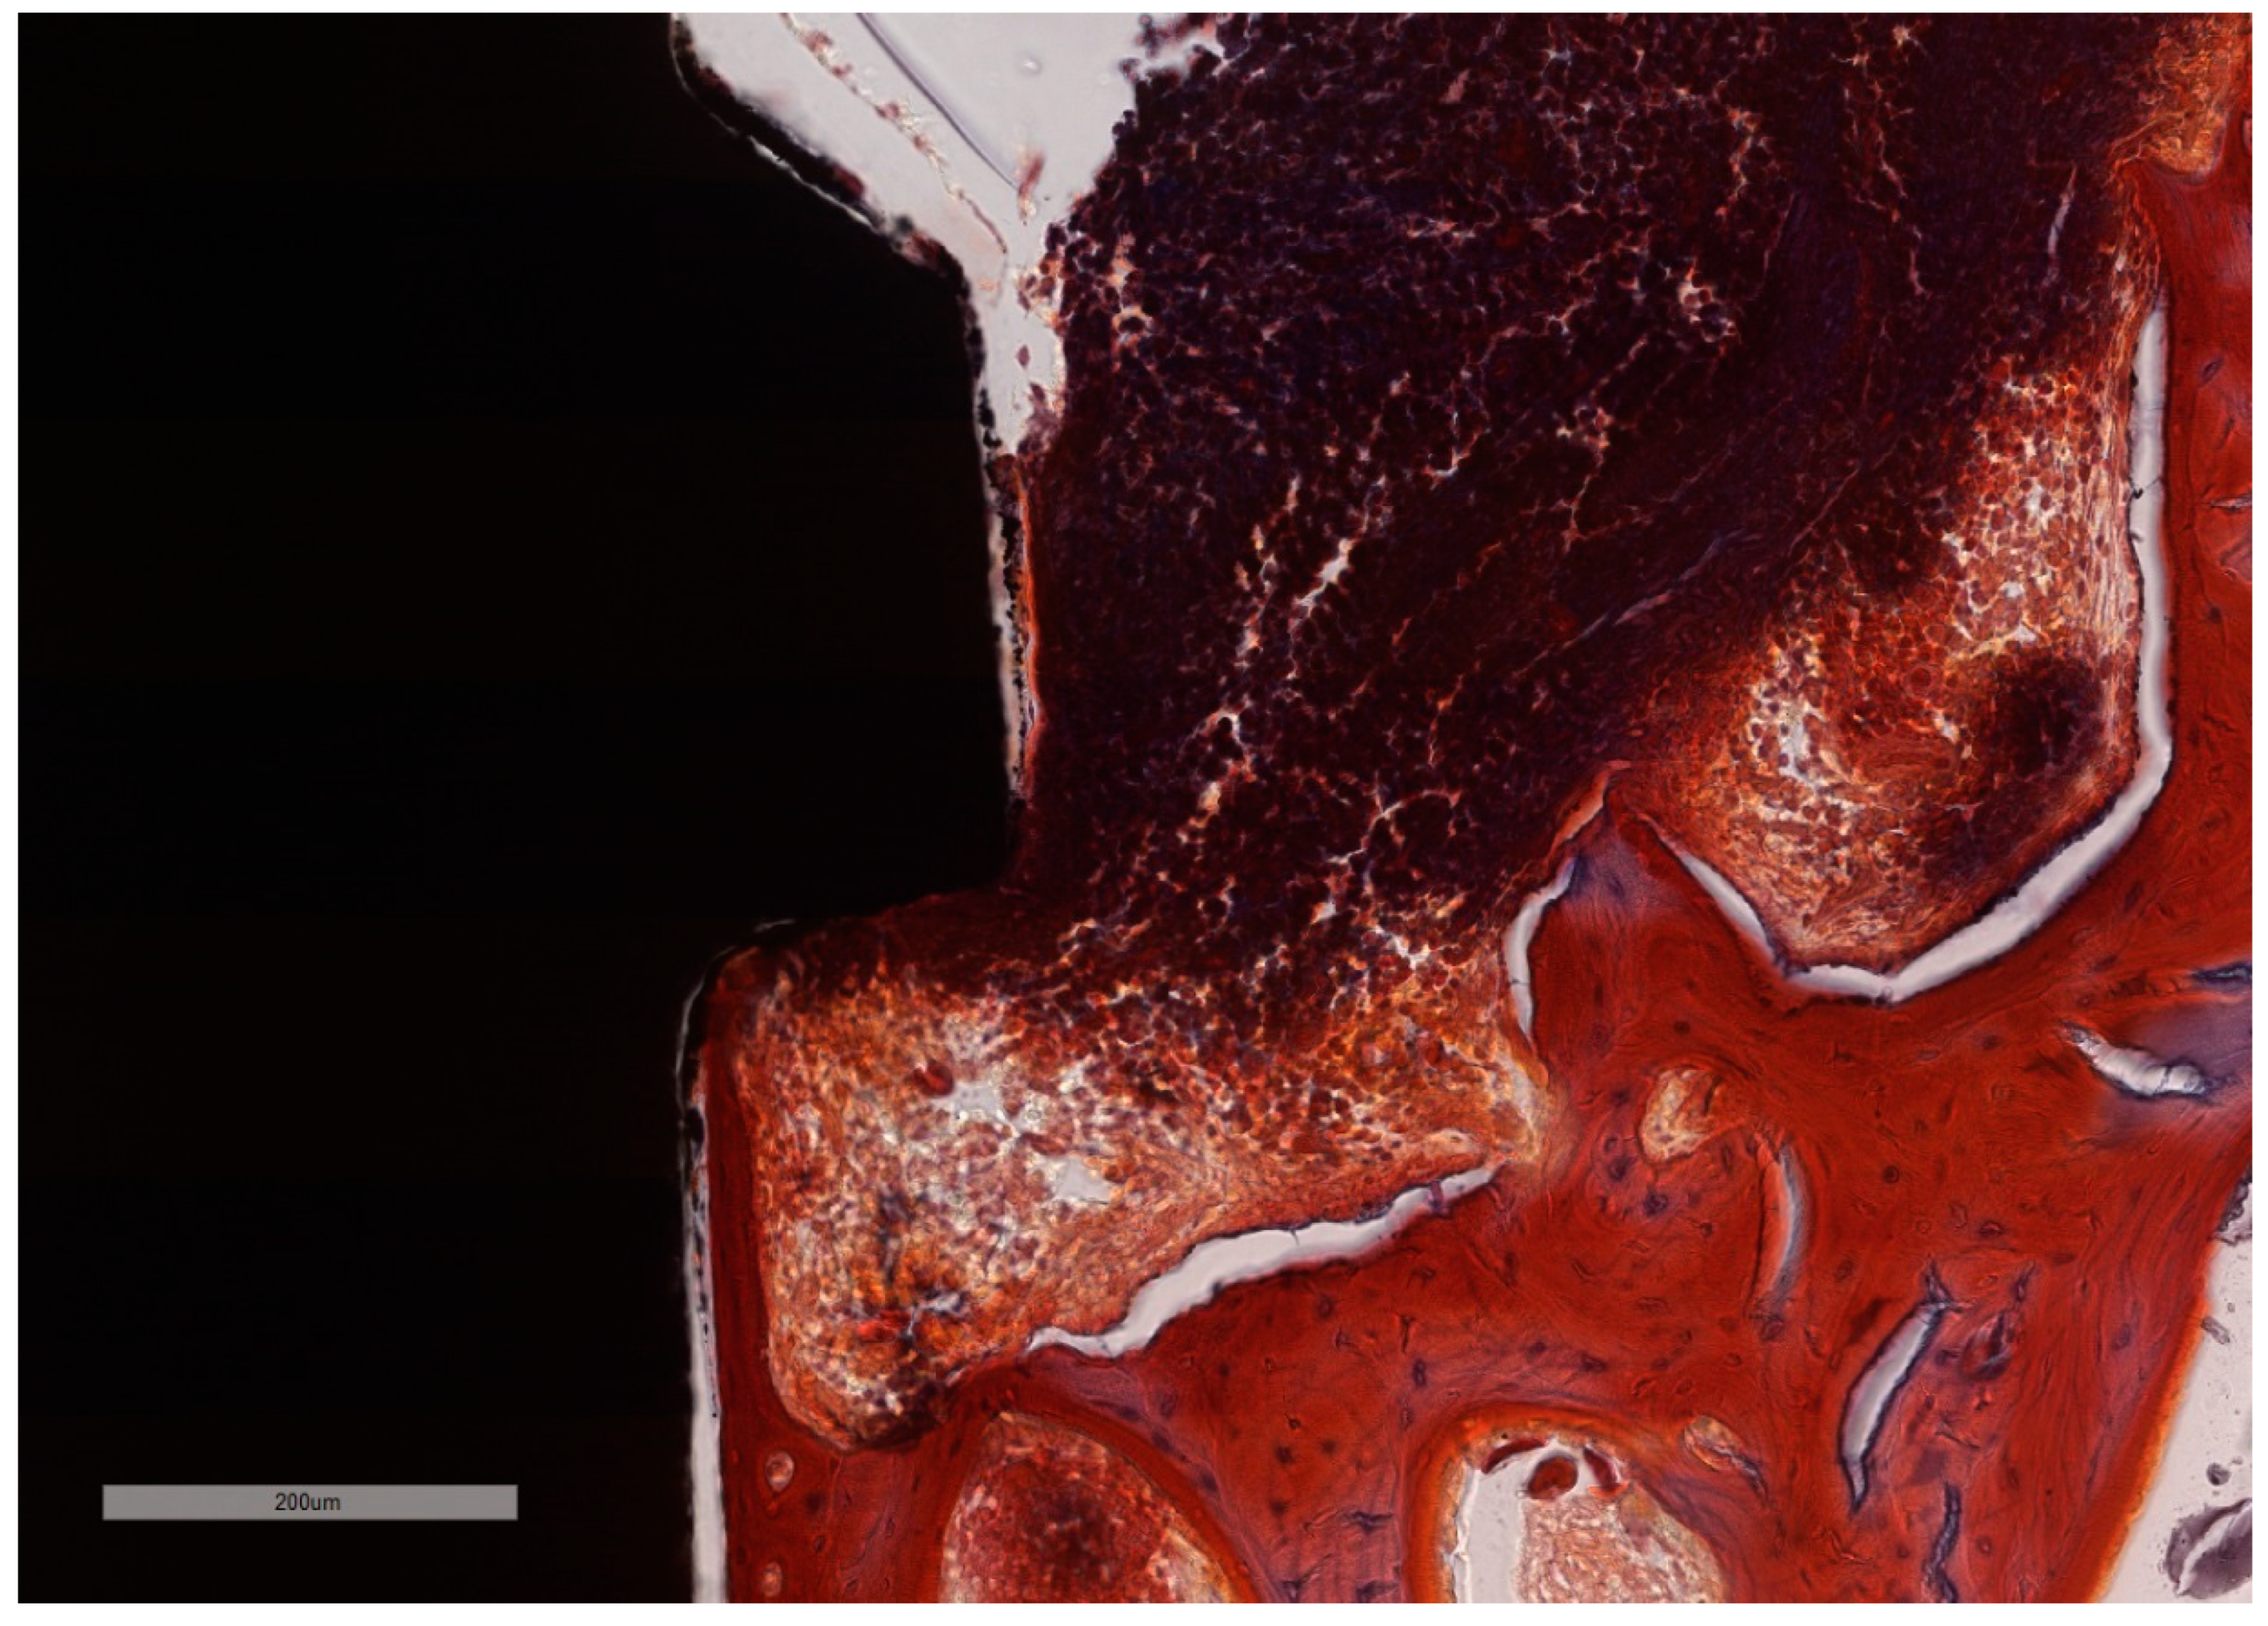

Figure 8. “Open wound” aspect of the ICT in contact with the implants surface and a total lack of the epithelial lining. ICT is diffusely present in the soft tissue and is seen to progress into the bone marrow, without any sign of fibrous encasement. The peri-implant sulcus is deep and the intimate contact between the soft tissues and the implant is below the BC level (implant #3, MGA, bar measure is 900 µm).

Figure 11. Bone in active phase of remodeling. ICT in simultaneous contact with the bone and with the implant surface with no squamous epithelium covering. Additionally, active bone remodeling is identified by the scalloped endosteal surface (Howship’s lacunae) (implant #1, MGA, bar measure is 200 µm).